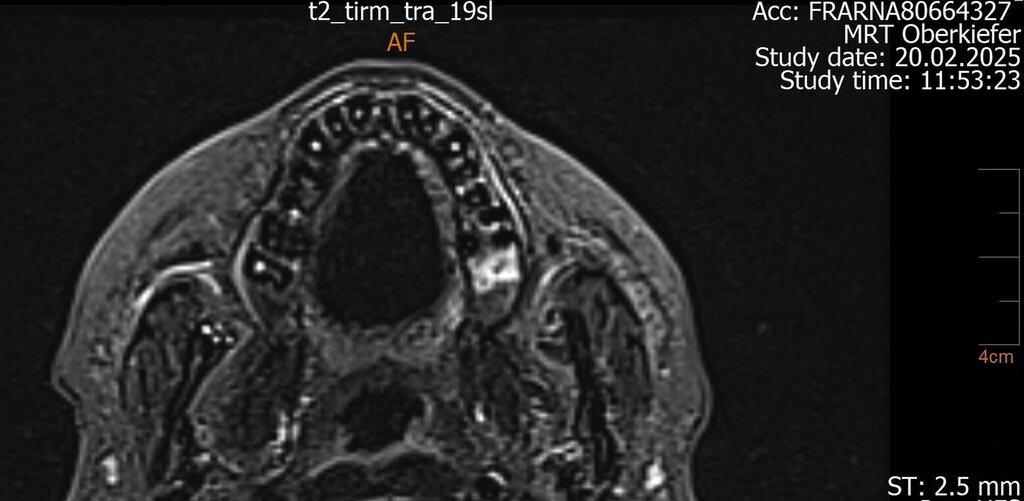

Der Wendepunkt erfolgte schließlich im Februar 2025 im Rahmen einer Kontrolluntersuchung bei der Hauszahnärztin. Diese nahm die langjährige Beschwerdesymptomatik ernst und veranlasste eine MRT-Untersuchung am Deutschen Zentrum für Dentaldiagnostik (DZD). Die MRT-Bildgebung ergab eine chronische Osteomyelitis im Bereich der Extraktionsregion von Zahn 27 sowie eine ausgeprägte apikale Ostitis an Zahn 26 mit vollständiger Verschattung der linken Kieferhöhle und Ausdehnung der Entzündung ins Siebbein und in die Stirnhöhle. Auch konnte durch den befundenden Radiologen eine interradikuläre Fistelung an Zahn 26 erkannt werden, weshalb die Sinusitis als odontogen eingestuft wurde (Abbildungen 4 bis 7).

Intraoperativ zeigte sich die interradikuläre Perforation im Sinne eines Fistelgangs zur linken Kieferhöhle (Abb. 8), die bereits präoperativ in der alio loco durchgeführten MRT-Bildgebung erkennbar gewesen war (Abb. 7). Zudem entfernten wir das Empyem und die pathologisch veränderte Schleimhaut sowie das Narbengewebe unter Schonung der noch intakten Schneider’schen Membran.

In speziellen Fällen kann ergänzend eine MRT sinnvoll sein – etwa bei unklarer Symptomatik, bei Verdacht auf Weichteilbeteiligung, bei einem chronisch-rezidivierenden Verlauf oder bei unzureichender Abgrenzbarkeit im DVT. Im vorgestellten Fall ermöglichte die MRT den Nachweis des interradikulären Fistelgangs zur Kieferhöhle und damit die korrekte Zuordnung des Entzündungsfokus.